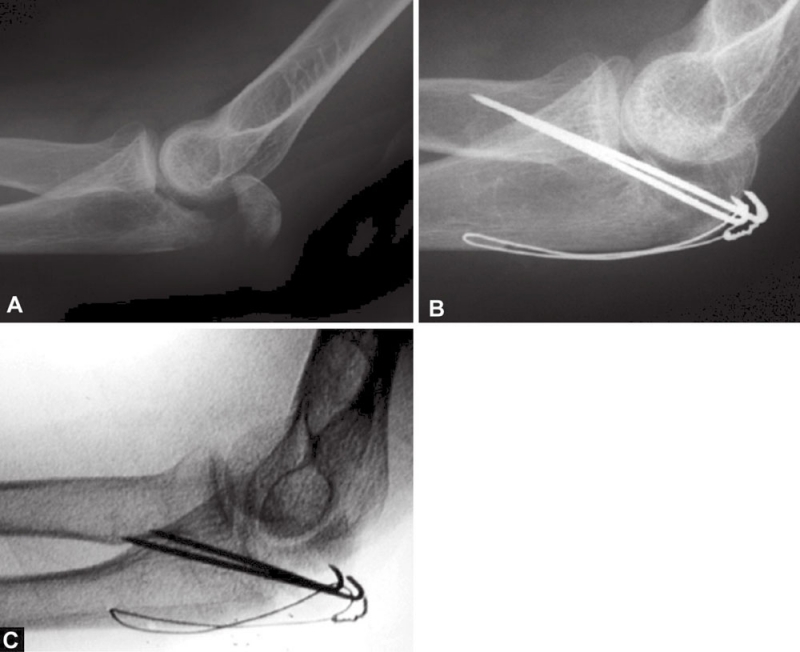

图2A~C关节面部分压缩非常不易觉察。有经验的医生会注意到鹰嘴曲线的变窄从而推断出压缩部分的存在。术中斜位X线片检查压缩骨折仍隐匿,仅在术后的X射线中越来越明显